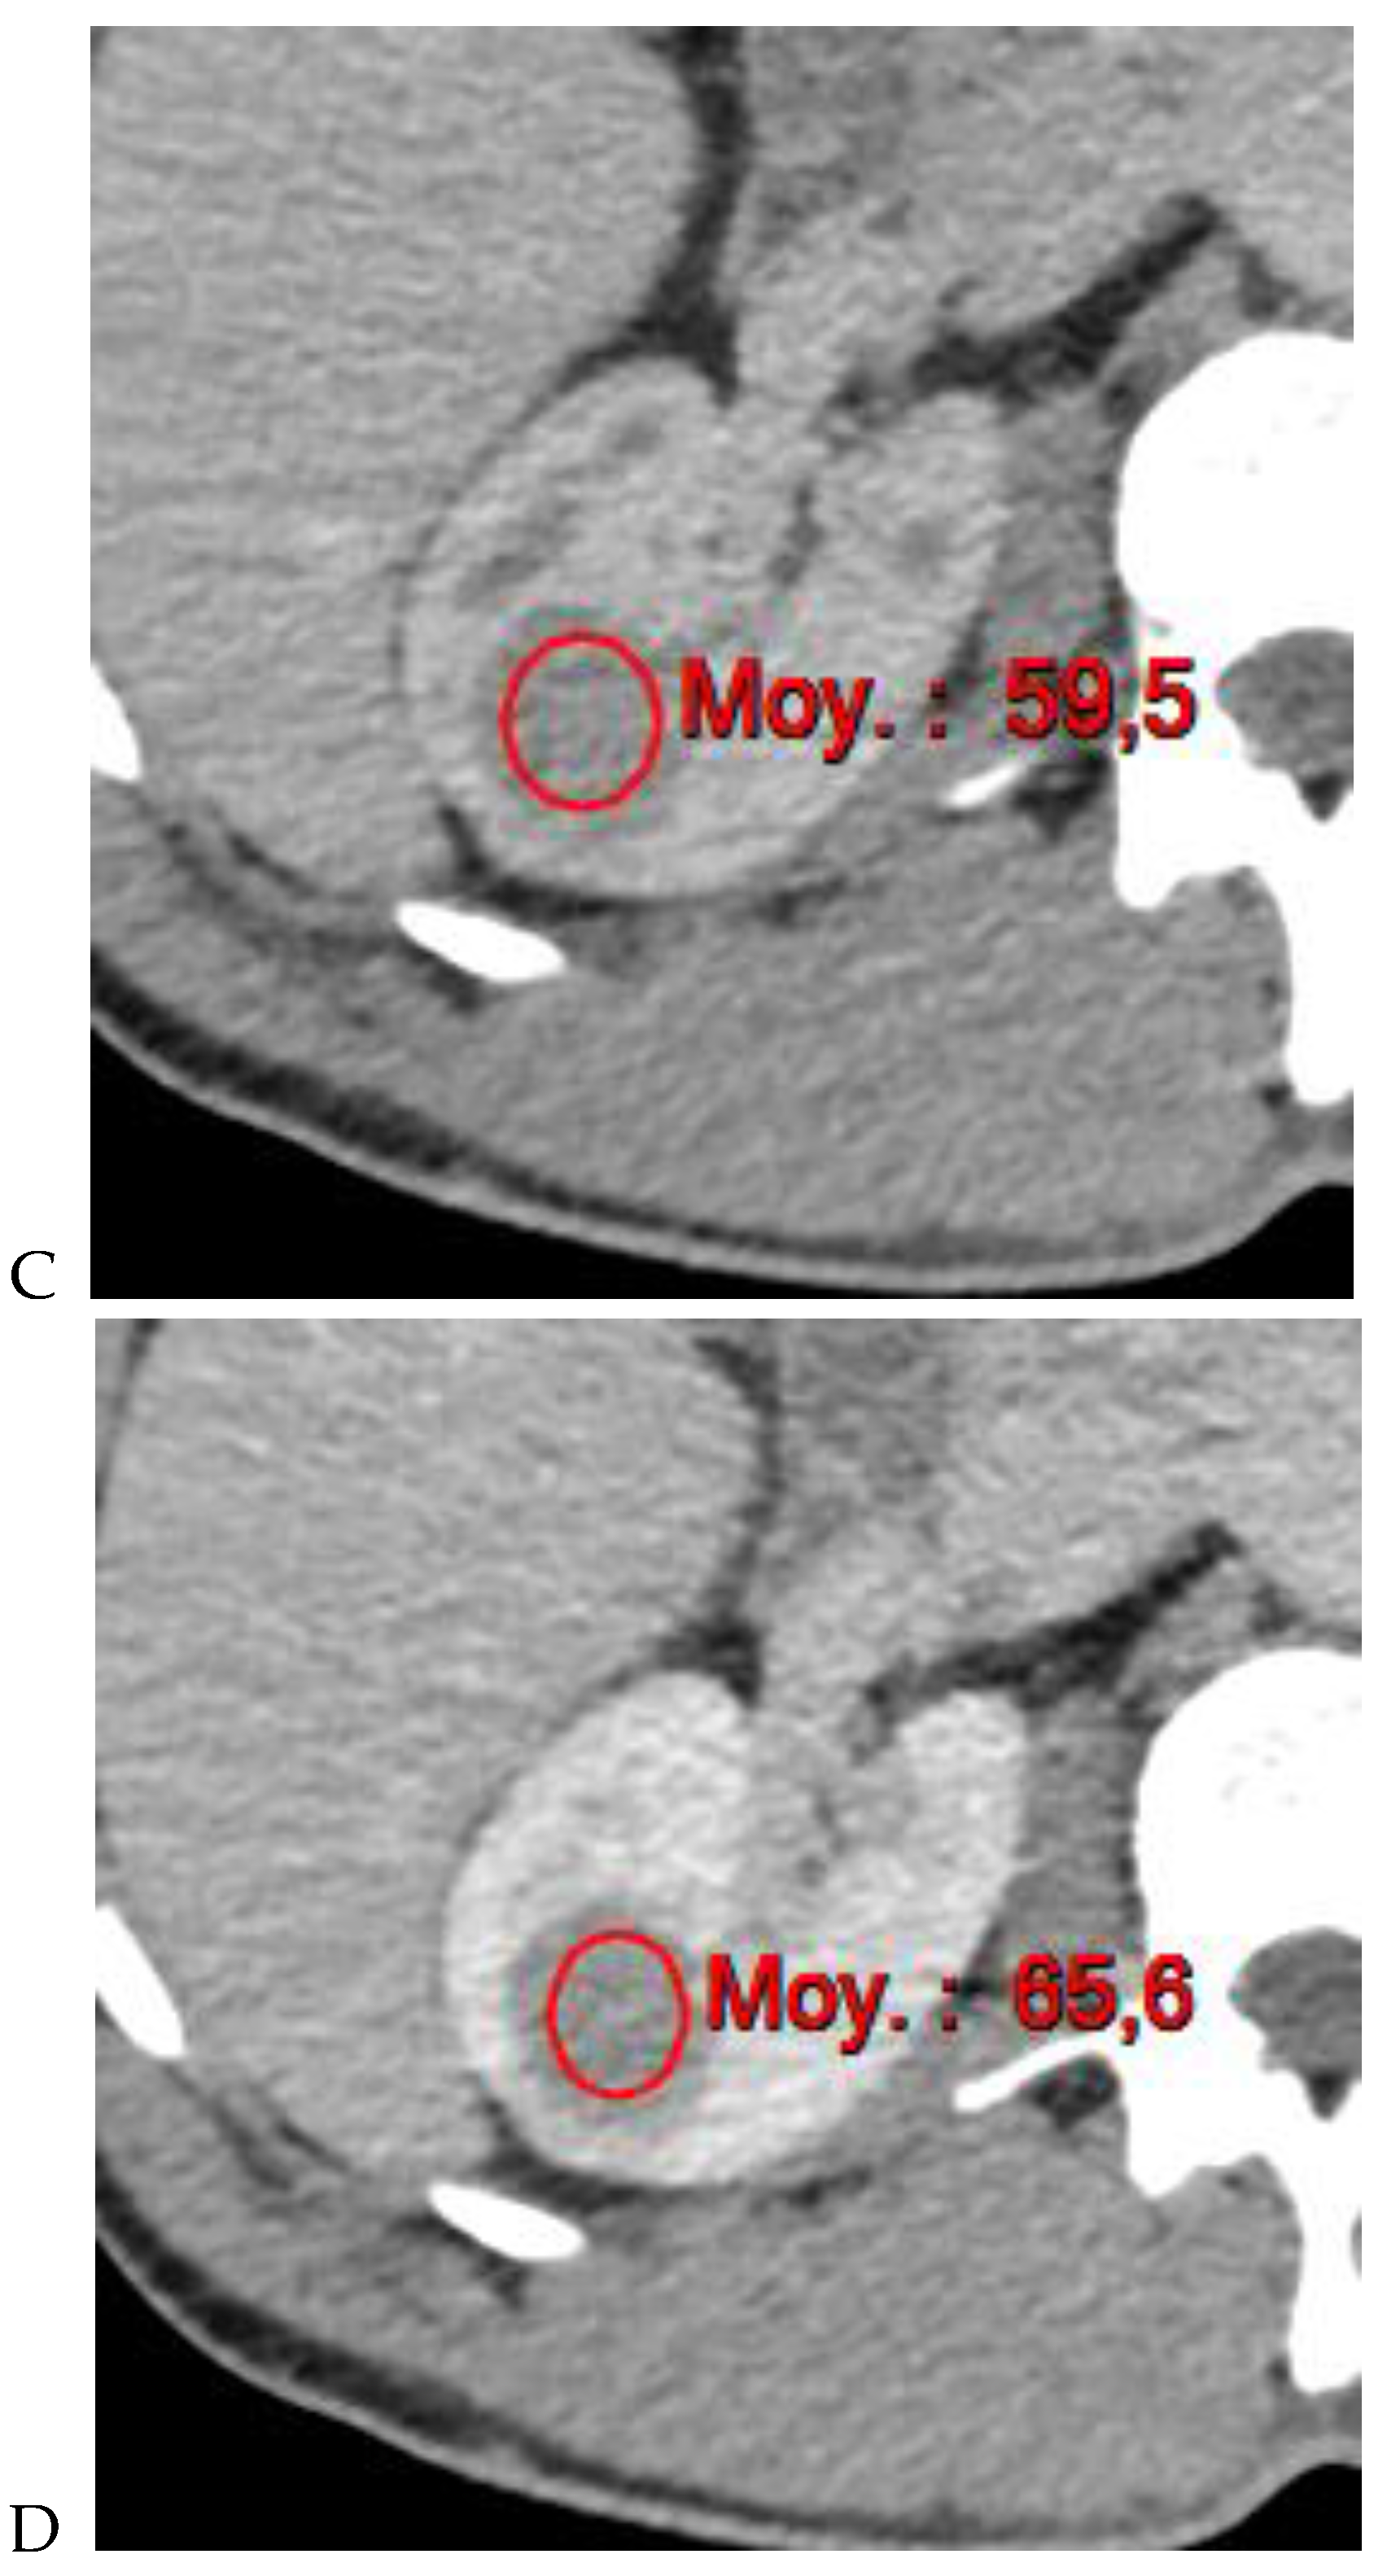

Oncocytoma in the right kidney of a 42-year-old man. (A) On the unenhanced image, the 4.8 cm lesion is isodense relative to the renal parenchyma. Enhancement is seen on the corticomedullary phase image (B), followed by washout on the nephrographic (C) and excretory (D) phase images. (E) Macroscopic view of the lesion after radical nephrectomy. Courtesy of Pr S. Ferlicot, Department of Pathology, Bicêtre.

Along with unenhanced images, enhancement on multiphasic CT provides a simple, noninvasive means of suggesting the histologic type of a renal mass. It is defined by an increase of 20 HU or more between precontrast and contrast-enhanced images [11]. In daily practice, an enhancement of <10 HU is considered to be characteristic of a cyst, 10–19 HU of an indeterminate mass, and >20 HU suggestive of a renal tumor. Young et al. [9] showed that the mean enhancement of clear cell RCC (Figure 1) was significantly greater than that of oncocytoma (Figure 2) and chromophobe RCC (Figure 3) in the cortico-medullary and excretory phases, and significantly greater than that of papillary RCC (Figure 4) in the cortico-medullary, nephrographic, and excretory phases. In their series, the mean attenuation values during the corticomedullary phase were 125.0 HU for RCCs, 106.0 HU for oncocytomas, 53.6 HU for papillary RCCs, and 73.8 HU for chromophobe RCCs. However, this quantitative information does not necessarily translate into clinically meaningful measures in daily practice due to the variability and overlap in HU measurements. In a recently published study of 87 patients with 93 pathologically proven papillary RCCs [31], most papillary RCCs presented as a hypovascular, circumscribed, solid renal mass; a few (17%) papillary RCCs presented as the newly defined Bosniak class IIF subtype.